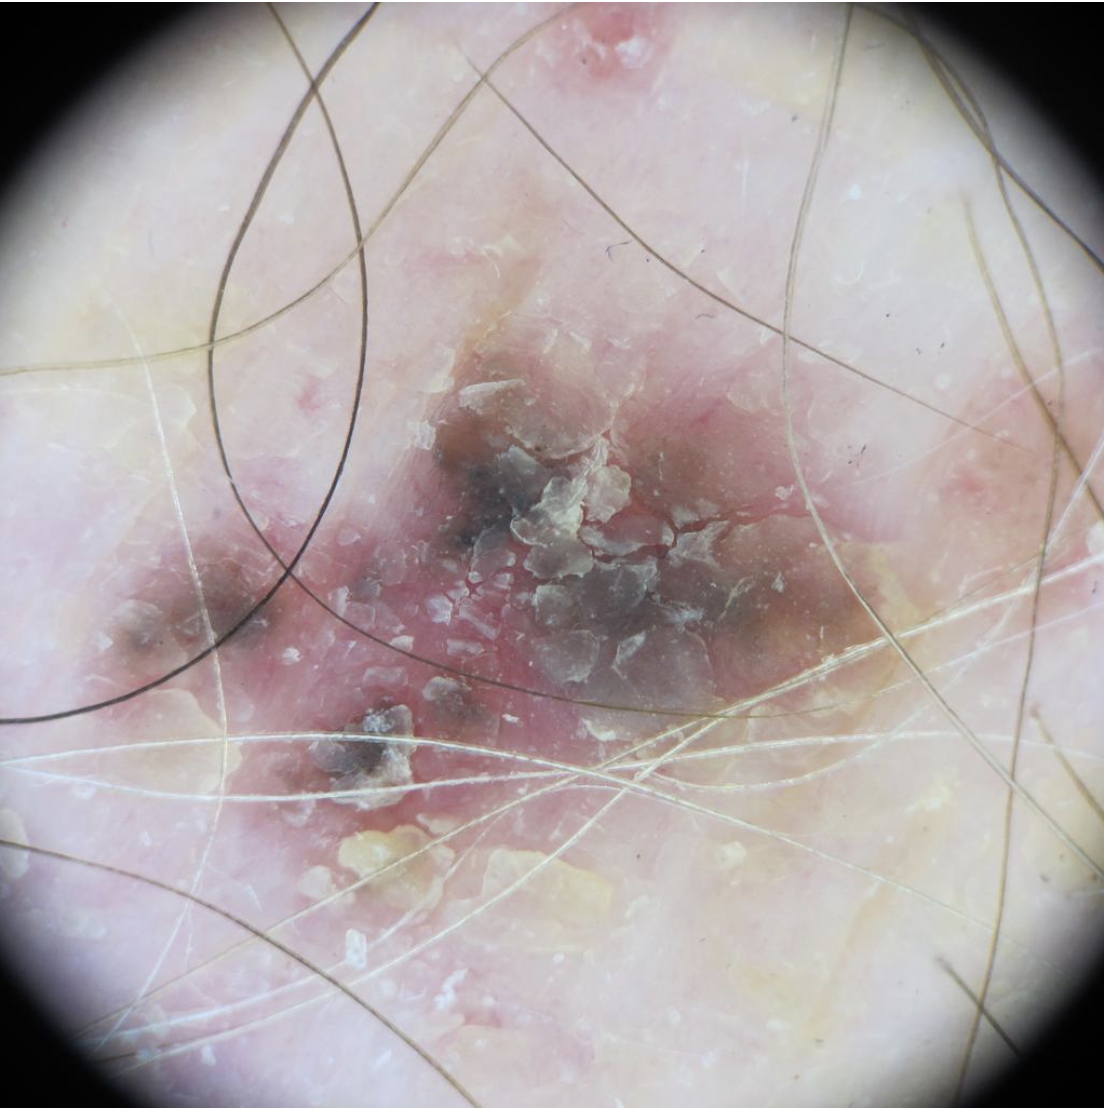

Actinic keratosis on posterior torso. Photo: International Skin Imaging Collaboration at isic-archive.com